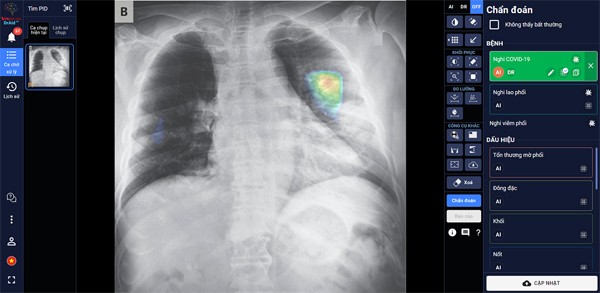

Đặc biệt, DrAid™ mang lại 4 giá trị ưu việt trong phát hiện và điều trị Covid-19 dựa trên ảnh X- quang ngực thẳng gồm: Phát hiện nhanh các dấu hiệu bất thường trong vòng chưa đầy 5 giây; Kết hợp cùng xét nghiệm PCR từ đó nâng cao độ chính xác, giảm thiểu tình trạng âm tính giả; Hỗ trợ đánh giá tiên lượng tình trạng bệnh nhân thông qua lịch sử hình ảnh chụp X-quang, để từ đó có hướng điều trị phù hợp; Hỗ trợ tăng tính nhất quán và chuyển giao kiến thức của bác sĩ từ tuyến Trung ương tới cơ sở.

| DrAid™ hỗ trợ đánh giá tiên lượng bệnh nhân Covid-19 dựa trên hình ảnh X-quang ngực thẳng |